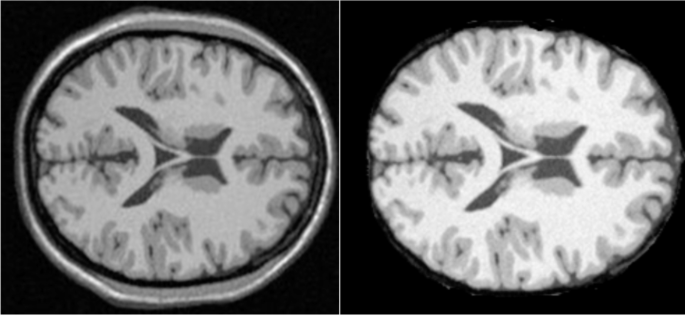

First, the MRI image is considered as input and skull stripping is performed on slice number 90 as a pre-processing step as shown in Fig. 2. On the skull stripped image, the new proposed Gaussian Kernelized Enhanced intuitionistic FCM (GKEIFCM) algorithm is applied for segmentation. The resultant clustering outputs are contrasted with the original images by using quantitative metrics to estimate the performance of the proposed method. The GKEIFCM method is proposed from IIFCM, which in turn developed from the IFCM. By the hybridization of IFCM, IIFCM methods, a novel GKEIFCM algorithm is proposed.

(a) Input MRI image slice 90, (b) Skull stripped image.

Segmentation of tissues in MRI brain images

The obtained results are verified for various MRI slice numbers 60, 65, 70, 75, 80, 85, 90, 95, 100, 105, 110,115, 120,125 respectively. The input and skull stripped images are shown in Fig. 2 for the slice number 90. This data-set includes a variety of noise levels (0–9%), T1-weighted images with various noise levels are used. The volume 1-mm slice thickness, 1 × 1 × 1 mm3 as voxel-size and voxel-resolution of 1-mm3, images are of dimension 181 × 217 × 181 voxels are used. The results are shown for the segmented images with 3% noise in MRI images for slice number 90 in Figs. 4 and 5 for grey matter and white matter respectively.